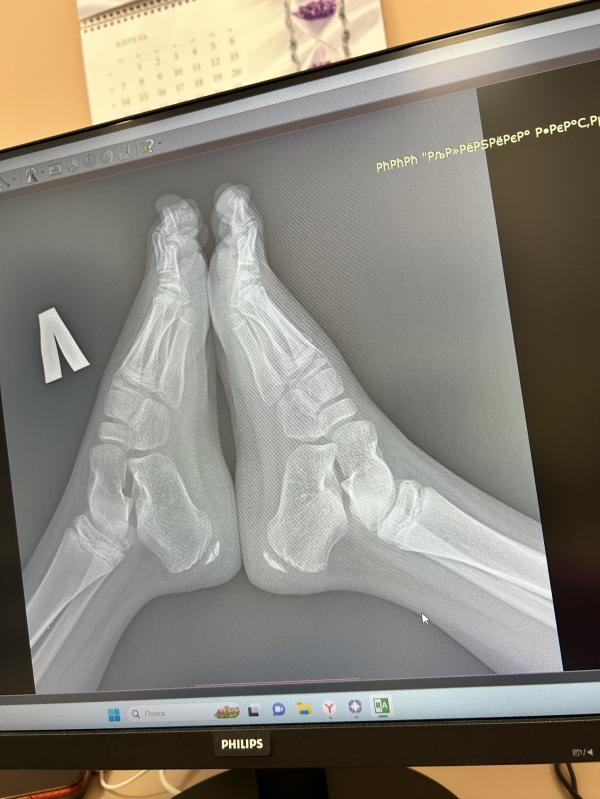

Всем привет! Сыну поставили болезнь Хаглунда-Шинца– остеопатия апофиза (бугра) пяточной кости.